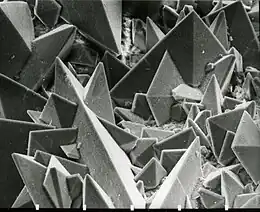

Calcium-containing stones

By far, the most common type of kidney stones worldwide contains calcium. For example, calcium-containing stones represent about 80% of all cases in the United States; these typically contain calcium oxalate either alone or in combination with calcium phosphate in the form of apatite or brushite.[25][52] Factors that promote the precipitation of oxalate crystals in the urine, such as primary hyperoxaluria, are associated with the development of calcium oxalate stones.[24] The formation of calcium phosphate stones is associated with conditions such as hyperparathyroidism[23] and renal tubular acidosis.[73]

Oxaluria is increased in patients with certain gastrointestinal disorders including inflammatory bowel disease such as Crohn's disease or in patients who have undergone resection of the small bowel or small-bowel bypass procedures. Oxaluria is also increased in patients who consume increased amounts of oxalate (found in vegetables and nuts). Primary hyperoxaluria is a rare autosomal recessive condition that usually presents in childhood.[74]

Calcium oxalate crystals can come in two varieties. Calcium oxalate monohydrate can appear as 'dumbbells' or as long ovals that resemble the individual posts in a picket fence. Calcium oxalate dihydrate have a tetragonal “envelope” appearance.[74]